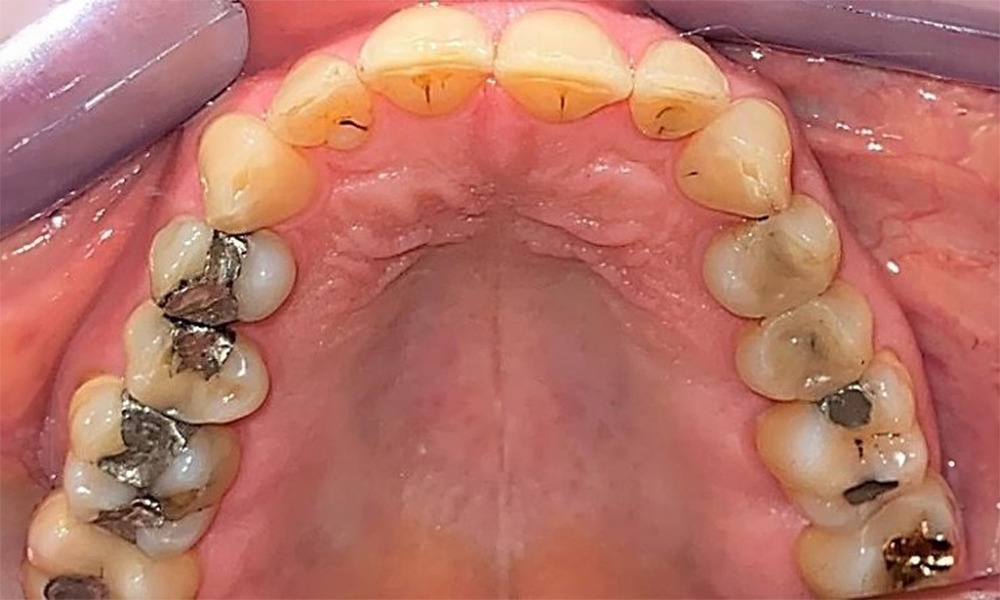

Occlusal view of the maxilla. Insufficient amalgam filling of 14 with a marginal gap.

Fig. 5 Occlusal view of the maxilla. Insufficient amalgam filling of 14 with a marginal gap. © Dr R. Krapf

The patient has a full dentition with 28 teeth, which includes amalgam and composite fillings in the molar and premolar regions. There is a visible clinical marginal gap present on tooth 14. Tooth 27 has an adequate gold inlay. There are also generalized attritions and abrasions. (Fig. 2, Fig. 3, Fig. 4, Fig. 5, Fig. 6)

There is fully dentulous adult dentition with generalized bone loss of between 20-50% and multiple areas of vertical bone loss. Radiological examination revealed no visible caries. (Fig. 7)